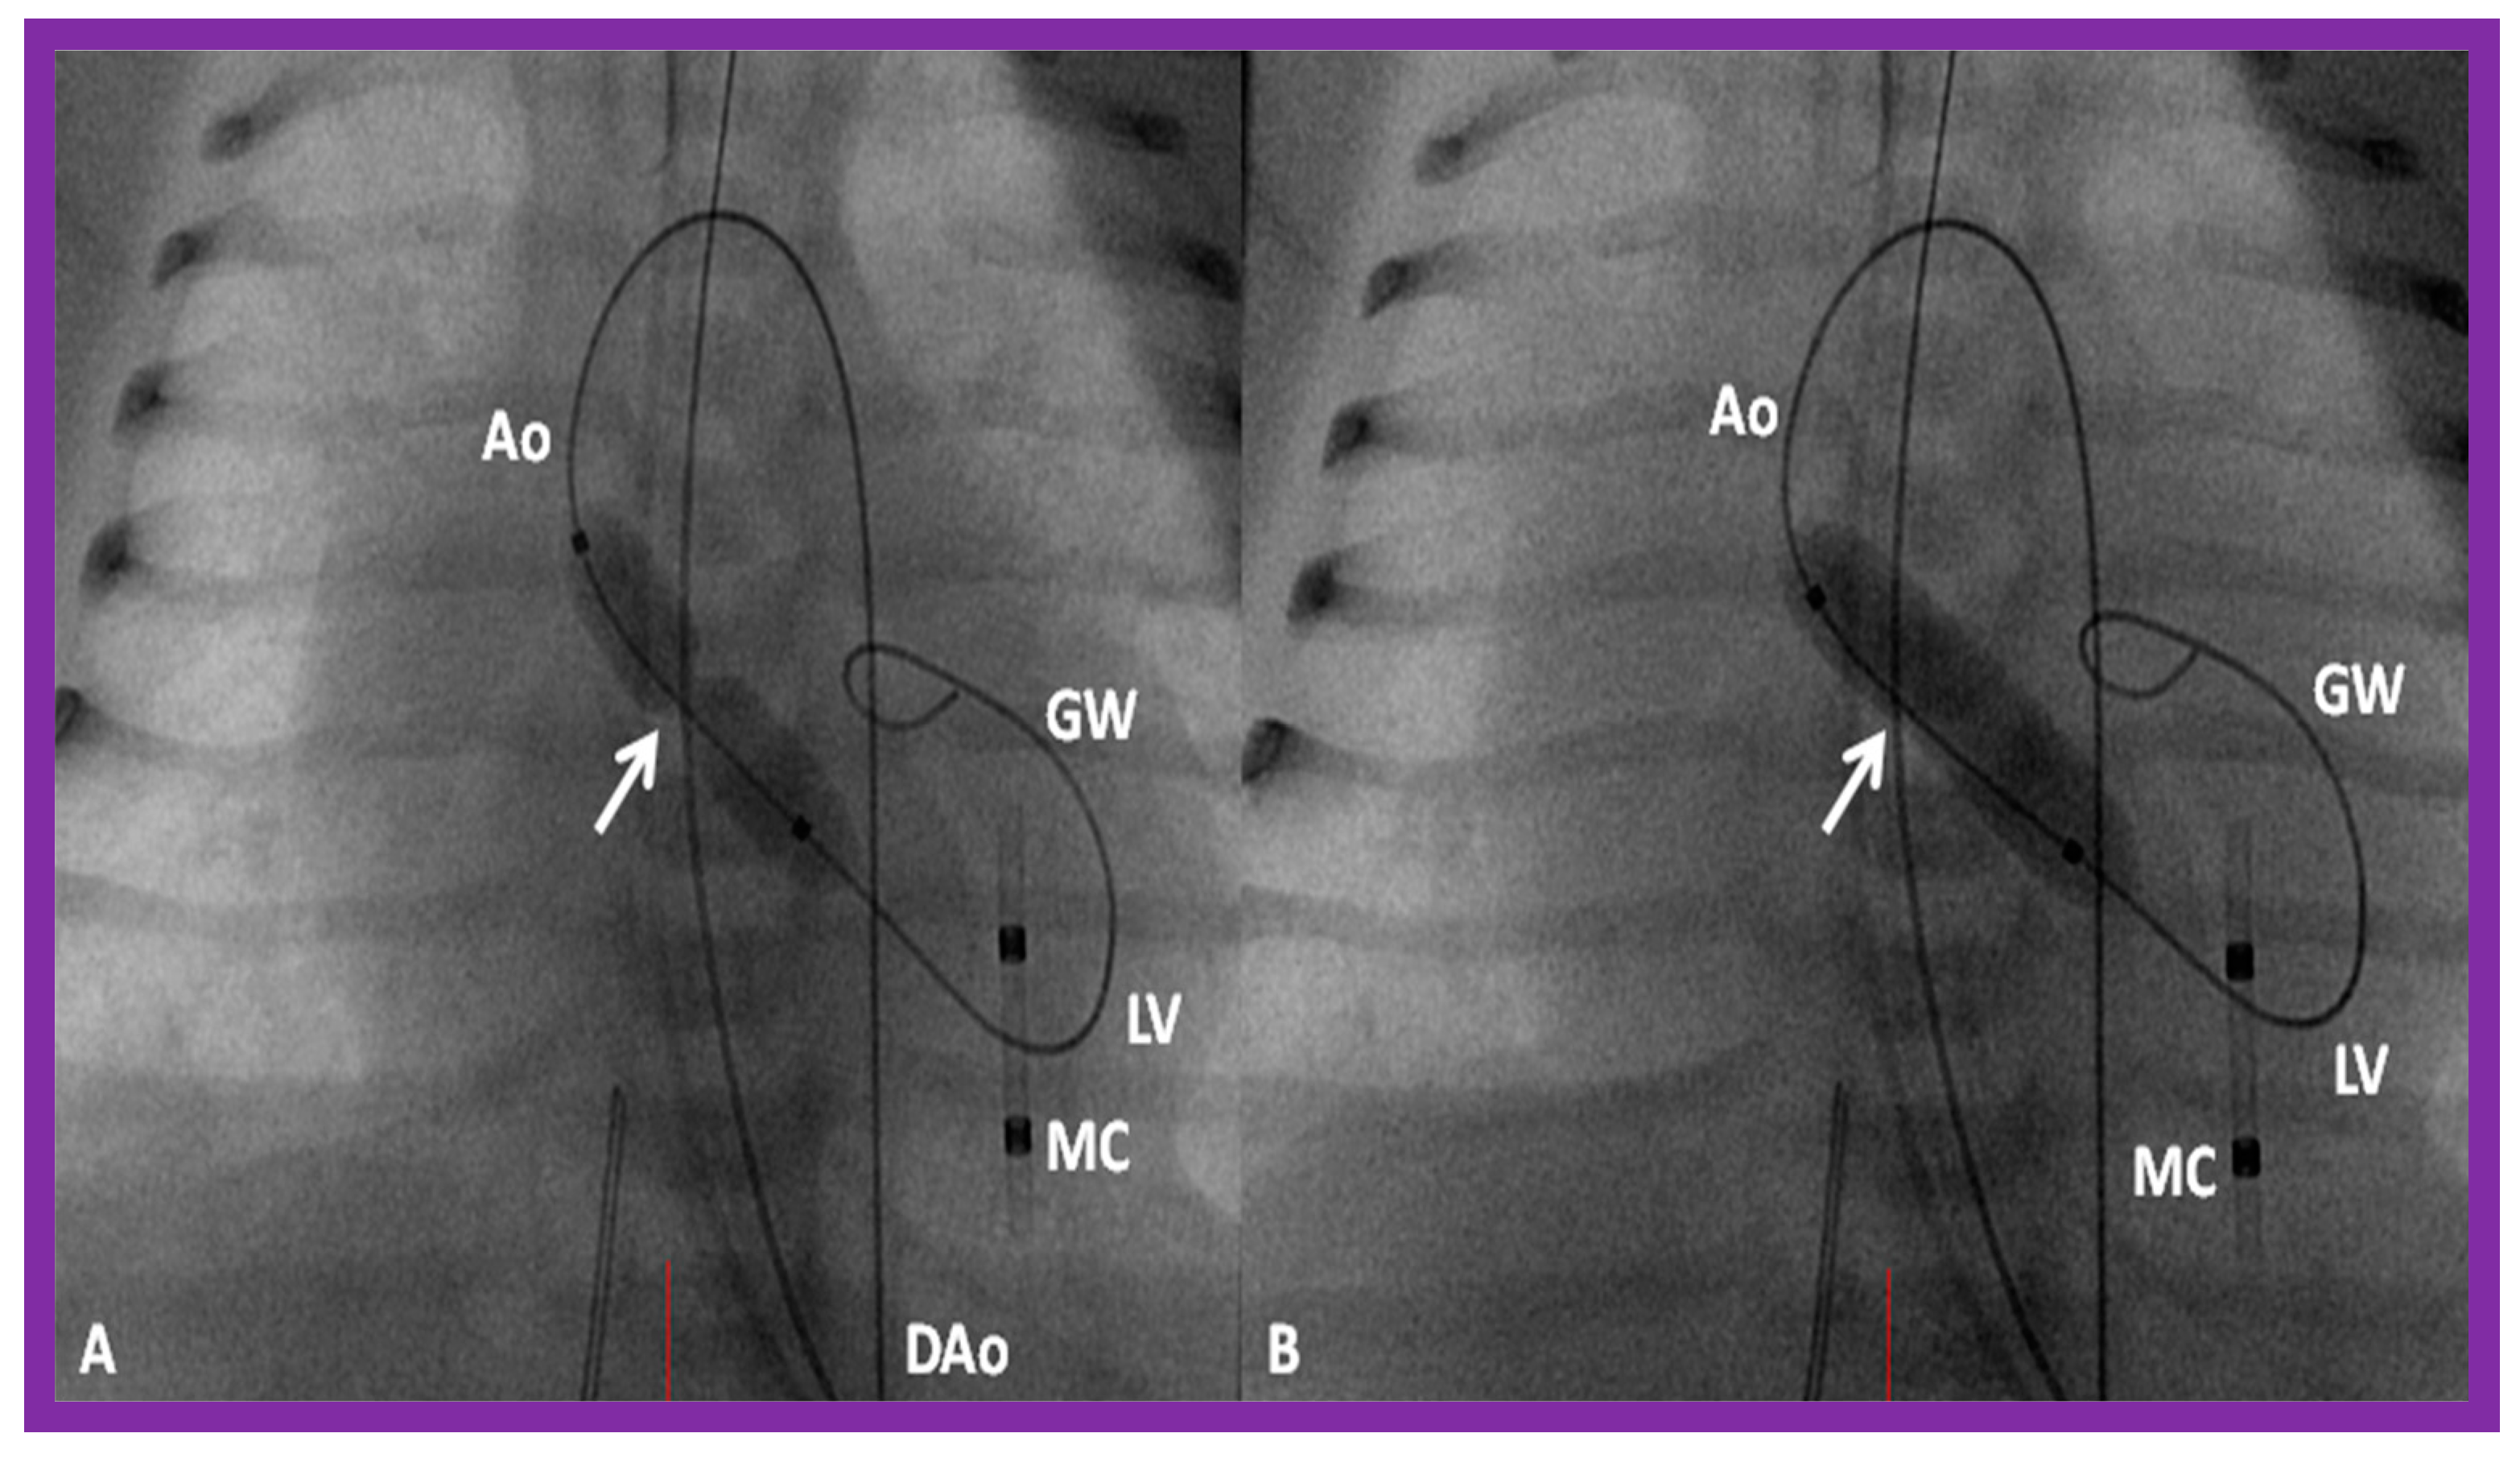

3.3. Aortic Coarctation, Native

3.4. Aortic Coarctation, Postsurgical